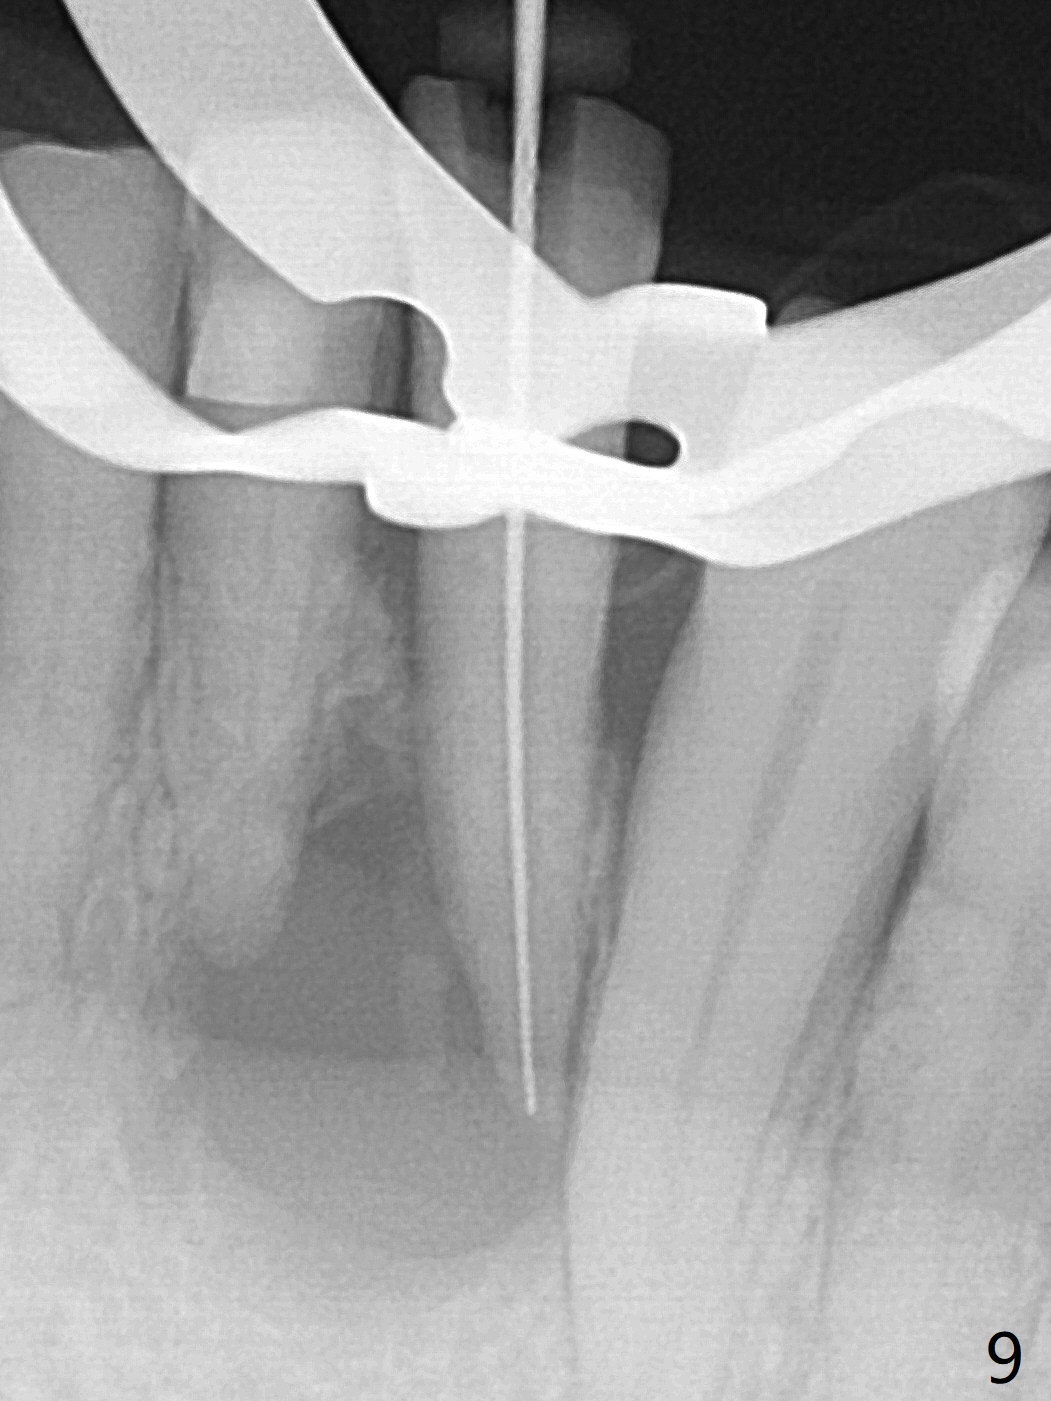

A 73-year-old woman has discomfort associated with #23 four months post Class V composite at #23-25 (Fig.1 C (*: Class V lesions)). Bone loss seems to be more severe lingually, especially at the crest (Fig.2 L). It appears that the apex of the tooth #24 is also in the large apical lesion (Fig.3). Class V composite is apparently continuous with the pulp at #25,24,23 (Fig.5-7). In contrast, Class V defect does not involve the pulp at #26 (Fig.4). If necrosis is confirmed clinically for #23 24 and 25, RCT will be conducted. Due to 7-day Amoxicillin taken for #3 implant, the patient feels that her tongue moves freely, as related to reduction in pain and swelling lingual to #23 (Fig.8 *). Endo ice test shows necrosis of #23 to 25. RCT is initiated at #23 (Fig.9) with buccal and lingual swelling. Endo may have to be at #24 with apicoectomy with PRF. The lingual swelling remains at #23, although there is no pain or purulent discharge 5 and 5.5 months post debridement (Fig.10,11). RCT is finished (Fig.12). Apicoectomy is pending with PRF. Less aggressive curettage will be done at #24 to maintain apical blood supply. Vitality tests have been done without conclusion.